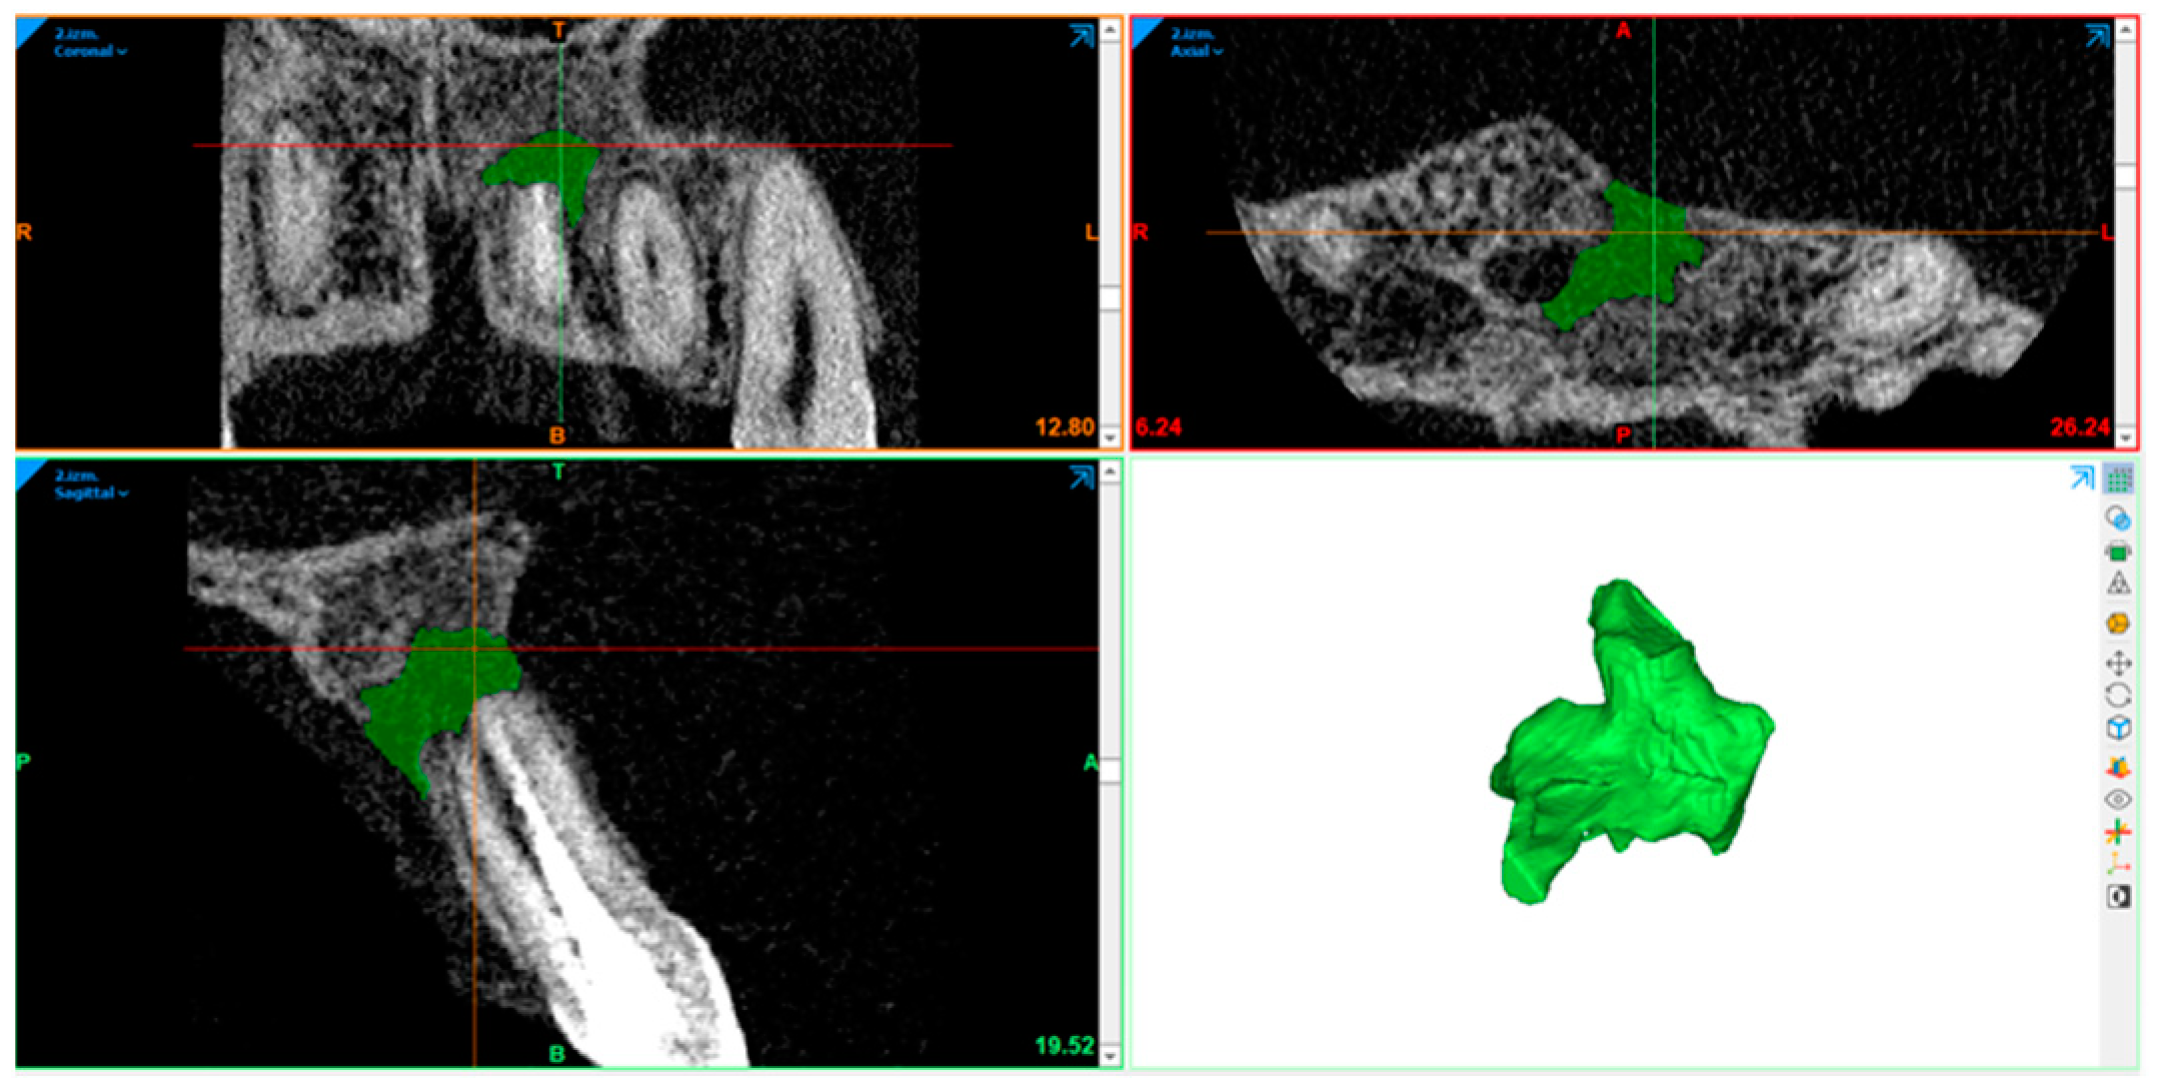

2.10. Radiography Acquisition: Volumetric Assessment

2.11. Statistical Analysis